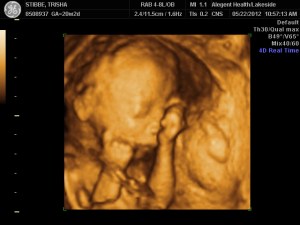

Ultrasound Day!